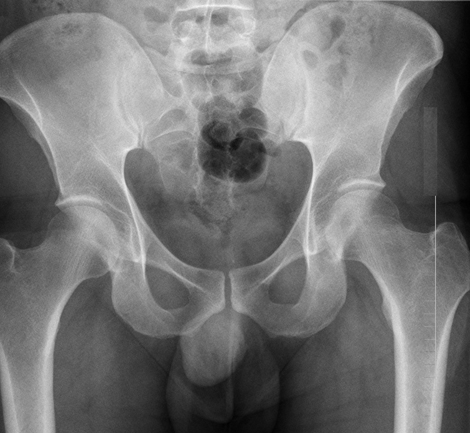

股骨颈(大胯)骨折,如果没有完全断开,或者断开的骨头茬(cha)子之间像两个齿轮的齿一样互相嵌插咬合在一起(我们称之为嵌插骨折),如下图。这时骨折断端之间还是有一定稳定性的。

白箭头所指处,即为股骨颈骨折部位,但因为嵌插而不明显

这个时候,患者虽然骨折了有点疼,但是却可以继续负重行走。很容易让患者误以为没有骨折,觉得只是软组织挫伤。